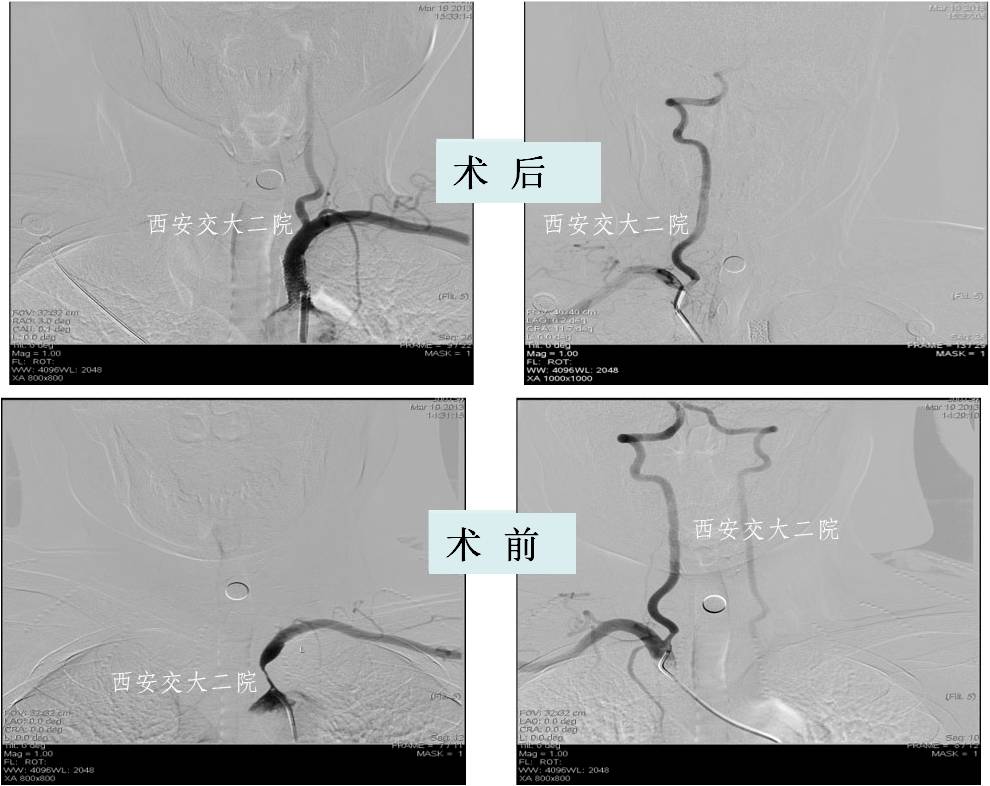

Case 2 右侧锁骨下动脉慢性闭塞再通术

》58岁,男;

》头晕、右上肢乏力4年,活动后明显;

》查体:右上肢皮温低,右侧桡动脉搏动弱,右上肢血压测不到。

Case 3 左锁骨下慢性闭塞再通(2015年)

》男,80岁,活动后头晕7年。

》5年前外院脑DSA发现左侧锁骨下动脉闭塞,右侧椎动脉开口狭窄,给予右侧椎动脉开口支架成形术,术后头晕稍有减轻,但活动后仍头晕,不能跳舞,患者坚决要求治疗。

Case 4 颈内动脉颅内段闭塞再通术

》女,57岁;

》左侧肢体无力1月于2014.1.8入院;

》诊断:脑梗死(右侧半卵圆中心)。